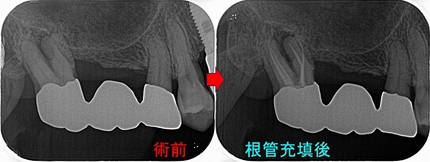

レントゲン

2026 EEdental MIH (1).jpg

かなり大きな虫歯があります。

術後3週間後に一度神経を残す方向でレジン充填を行い

痛みなどが出てしまったら、後で神経を取る処置を行なうと説明

2026 EEdental MIH (2).jpg

特殊な削り方をしてレジン(プラスチック)を詰めました。

親知らずの影響か、セメント質の肥厚が見られました。